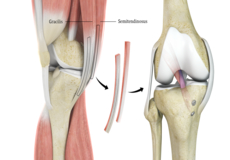

Hamstring Autograft

ACL reconstruction with hamstring autograft method is a surgical procedure to replace the torn ACL with part of the hamstring tendon taken from your leg. The goal of ACL reconstruction surgery is to tighten your knee and restore its stability.